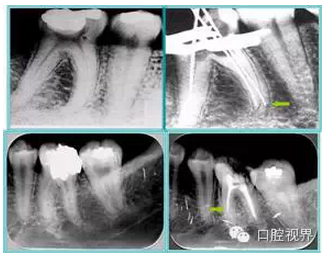

左圖和上圖為干髓治療后牙齒,齲齒疏通后進(jìn)行根管充填。

如圖為塑化加根充處理后牙齒 X 線片。

右圖箭頭處示臺(tái)階形成。